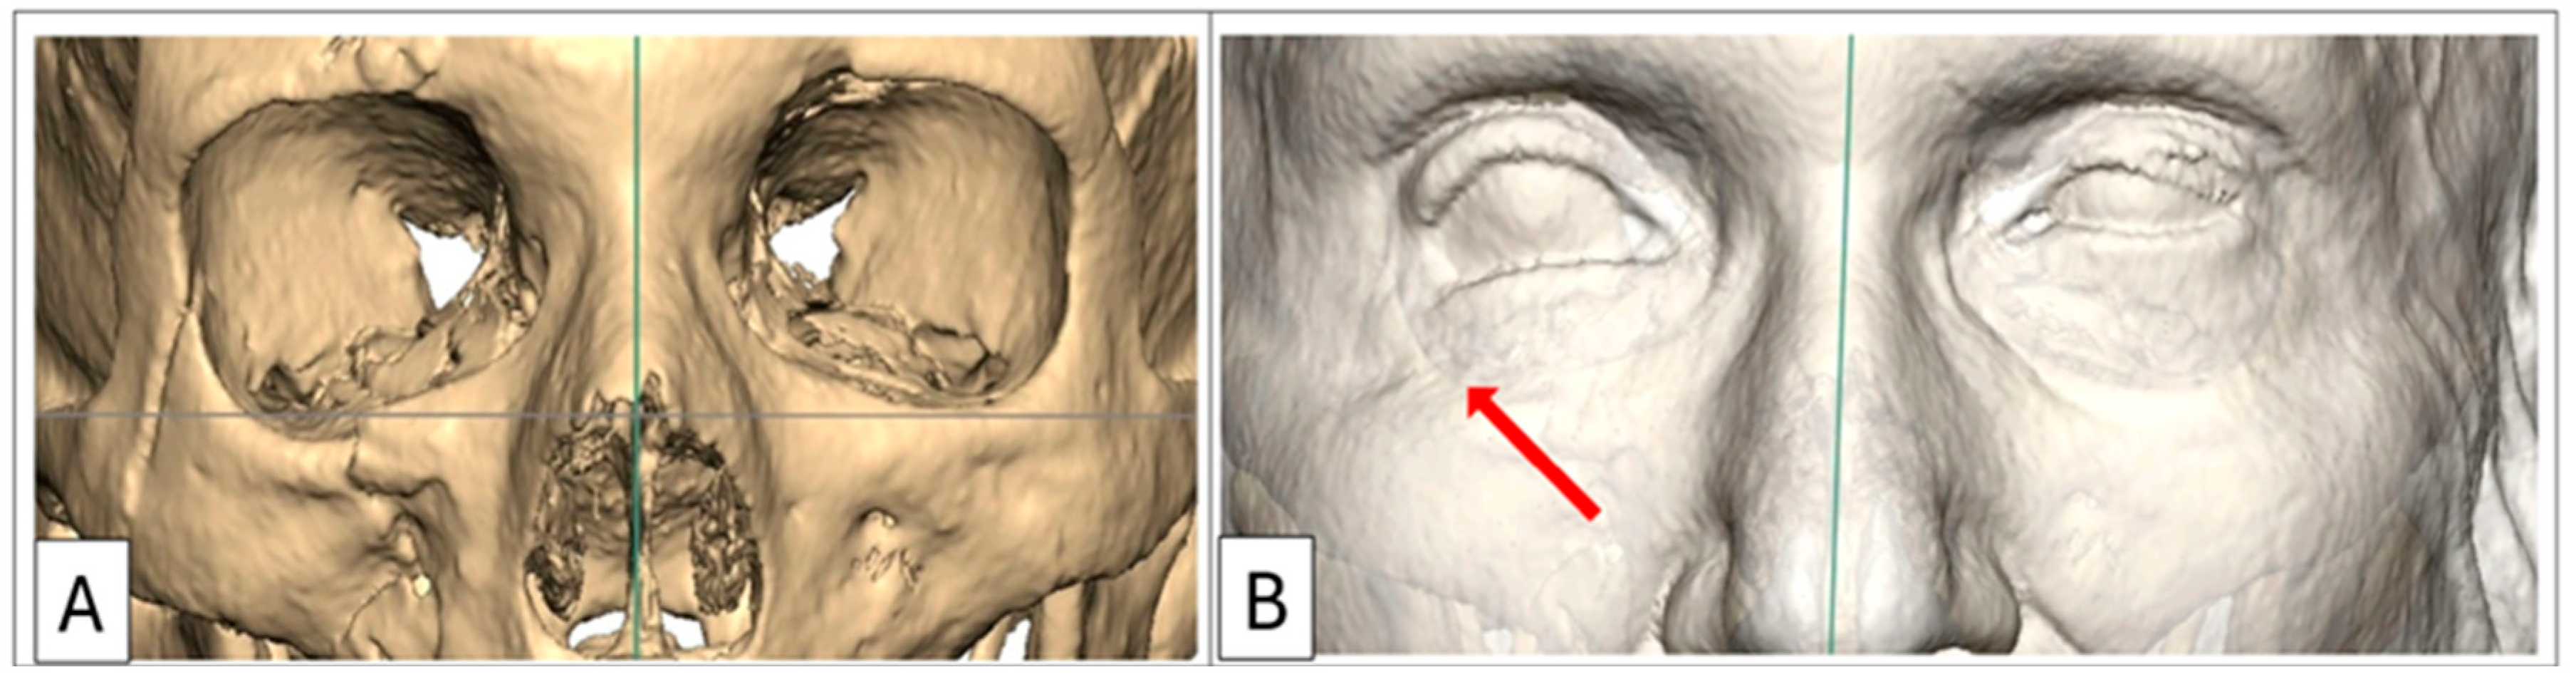

A comprehensive assessment of the orbitozygomatic complex allows for the design and inclusion of adjunctive implants, such as orbital rim and malar onlays, into the reconstruction process. Orbital rim and malar implants primarily address cosmesis. Therefore, orbitozygomatic reconstruction not only addresses functional aspects but also addresses cosmetic concerns such as upper eyelid pseudoptosis as a consequence of globe recession, which may alter the upper eyelid contour and deepen the superior tarsal fold [6]. Similarly, lower eyelid malposition—manifesting as retraction—often arising from a combination of scarring, soft tissue contraction, and, critically as in Case 1, due to inferior displacement of the lateral and infraorbital rim, can also be addressed (Figure 1) [7,8].

Figure 1. Case 1: Preoperative 3D-CT scan demonstrating lower eyelid retraction due to traumatic deformity (red arrow), requiring an infraorbital rim onlay implant and a lateral tarsal strip canthoplasty. Inferior displacement of the right lateral and infraorbital rim, (B) bone window, (A) soft-tissue window.